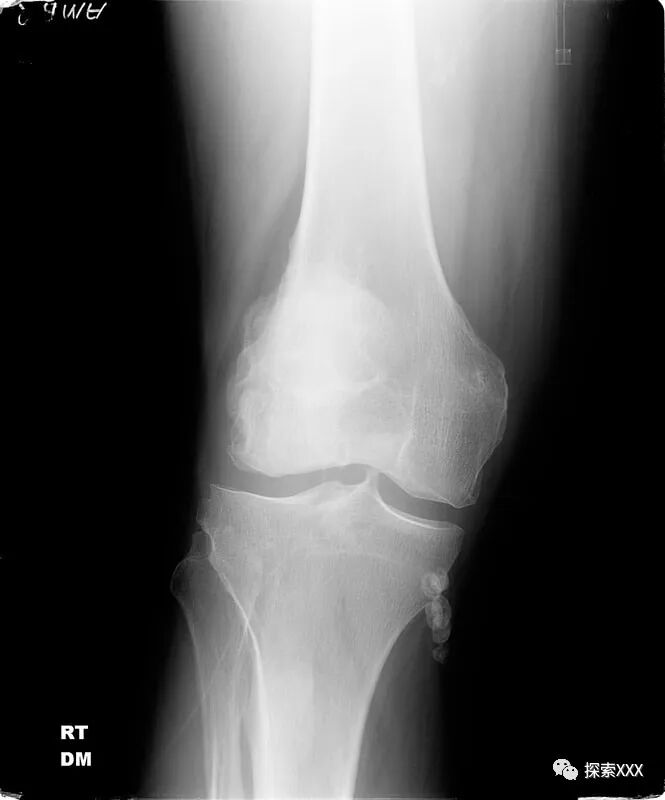

特里·洛夫莱斯的腿部异物

2017年11月16日,当特里早上醒来时,感到双腿胯部和膝盖疼痛。之后他发现腹股沟两侧都出现了圆形的瘀伤,右侧的挫伤呈花瓣状,中间还有一个洞。随后的X光检查显示,金属物体已从他的右大腿上消失,但两根细长的金属丝仍留在他的肌肉中。